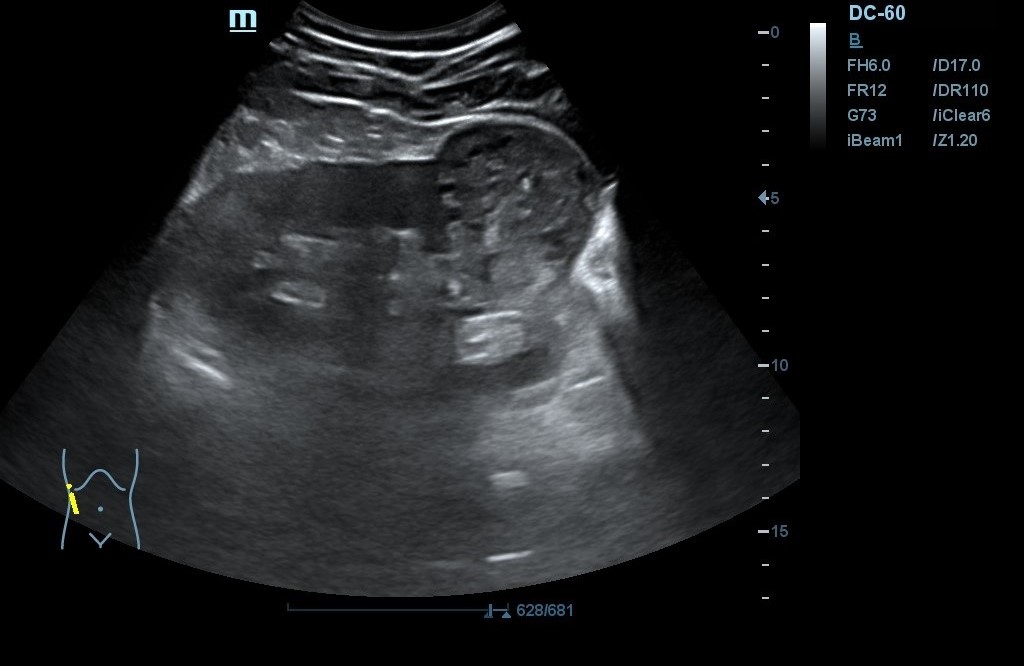

- POCUS: Lesión en polo inferior de riñón derecho (RD) de 6,2 x 5,02 cm de diámetro, con neovascularización y zonas hiperecogénicas. No signos de hidronefrosis. Disminución del flujo venoso con Doppler pulsado. Resultados compatibles con masa renal sólida a filiar. RI sin alteraciones. Jets vesicales presentes. Próstata de contornos regulares y ecogenicidad homogénea. Volumen prostático de 44 cm3.